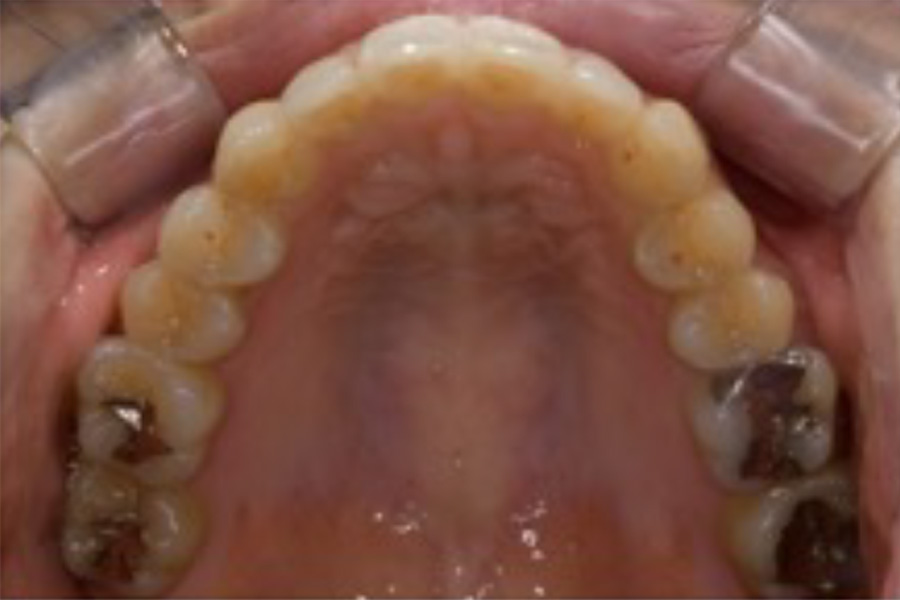

治療前

主訴 右上が気になる。下顎の歯並びを治したい。

治療内容 目立ちにくいマウスピース矯正(非抜歯矯正)

歯と歯の間に隙間をつくることにより、歯列弓を広げながら治療を行いました。